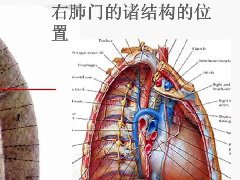

肺隔离症:易误诊为肺癌的占位性病变,肺穿刺禁忌!  肺段与肺内管道应用解剖

肺段与肺内管道应用解剖  肺转移瘤的十种不典型CT表现